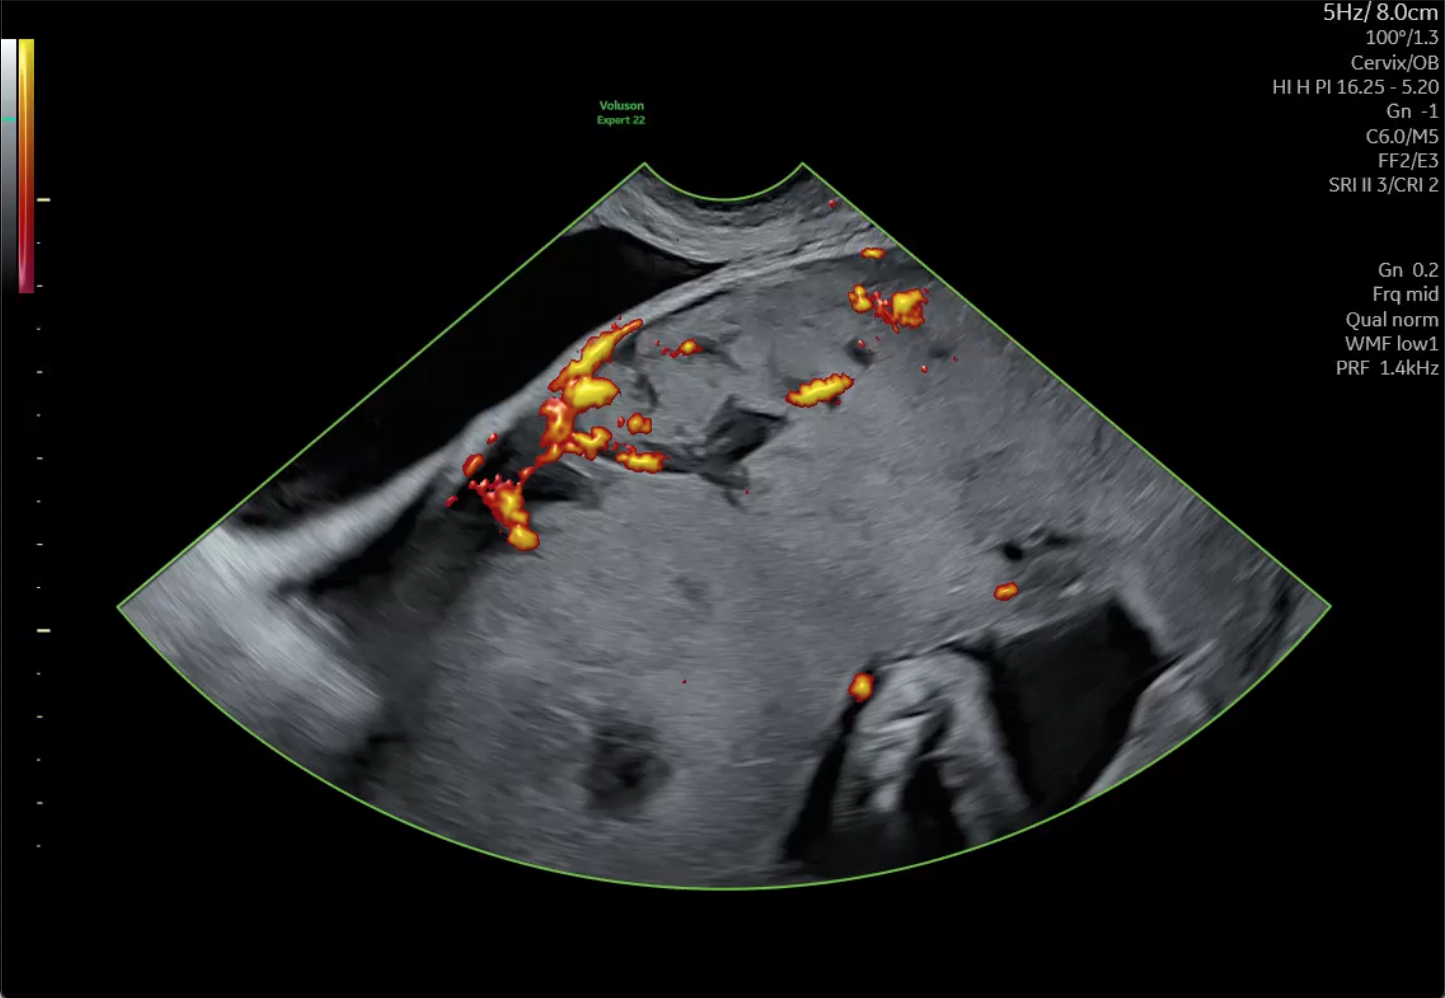

Potential Placenta Accreta

A placenta previa paired with suspected accreta was identified and tracked throughout this pregnancy. With a previous history of two cesarean sections along with a suspected accreta and previa, a third cesarean was scheduled for 34 weeks. The delivery plan would also involve an immediate hysterectomy given these indications.

When the patient delivered, everyone was surprised to discover no accreta, although placenta previa was still present. The patient and baby were both healthy, and the hysterectomy was not performed.